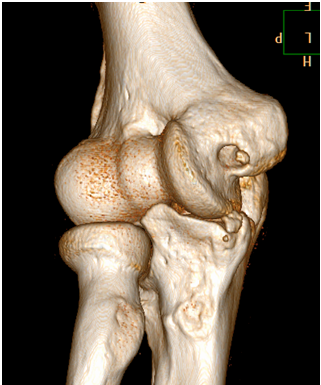

Computed Tomography

Last year we performed nearly 2,500 adult non-emergent MSK CT examinations at our Memorial and University Campuses of UMMMC and Marlborough Hospital. In addition to routine diagnostic CT exams, we also perform specialty MSK studies using CT, including:

Last year we performed nearly 2,500 adult non-emergent MSK CT examinations at our Memorial and University Campuses of UMMMC and Marlborough Hospital. In addition to routine diagnostic CT exams, we also perform specialty MSK studies using CT, including:

- CT arthrograms (Marlborough Hospital and Memorial Campus)

- CT guided soft tissue and bone tumors of the extremities (University Campus)